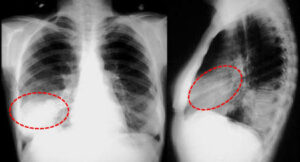

Основные причины появления кальцинатов в легких

Течение многих острых заболеваний паренхиматозных органов неизбежно приводит сначала к фиброзу, а затем к кальцификации. Кальцификаты в легких образуются в результате длительного воспаления. Процесс кальцификации чаще всего является защитным механизмом организма для уменьшения инфекции. В результате болезнь перестает прогрессировать, но пораженные части органов теряют свои функции. Причины появления Кальцификации в легких вызваны длительным воспалением. Основные …